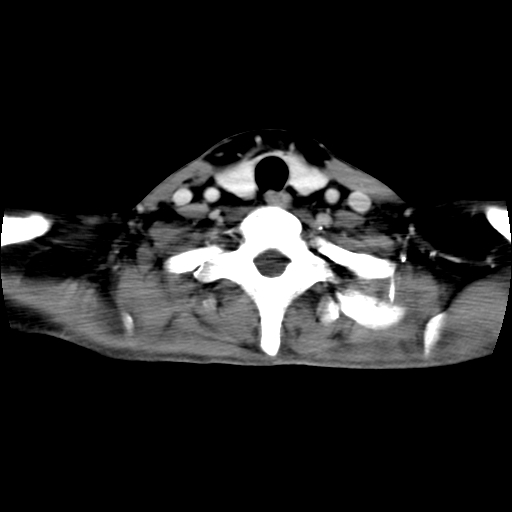

标题: CT24019:男,45岁,发现颈部肿物5个月。 [打印本页]

男,45岁,发现颈部肿物5个月,彩超示:双侧颈部及下颌部软组织增厚。

考虑双侧颈项部良性对称性脂肪增多症。